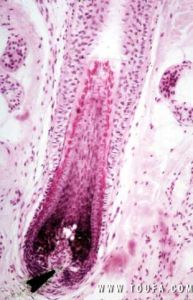

毛囊微觀結構毛囊幹細胞最重要的特點之一就是慢周期性,而且可以有無限多次細胞周期。當暴露於帶有核素活其他標記的核苷酸時,細胞在DNA合成的過程中攝取標記核苷酸而將標記整合到DNA中。由於幹細胞的細胞周期長,這樣的標記可以維持相當長一段時間。正是由於幹細胞的這一特點,有人便將它稱為標記滯留細胞(label-retainingcells,LRCs)。

實驗證實,LRCs具有幹細胞的特徵:其超微結構及生化特徵方面均具有分化細胞的特點,體積小,細胞器少,克隆形成能力高,細胞周期慢,無限次分裂。之前,研究者通過這種方法已經將成體毛囊幹細胞定位於隆突部。從形態學上看,隆突細胞體積小,有捲曲核,透射電鏡檢查發現其胞漿充滿核糖體,而且缺乏聚集的角蛋白絲,細胞表面有大量微絨毛,是典型的未分化或“原始狀”細胞。其他實驗還證實,毛囊上部角質形成細胞比下部細胞的體外增殖能力強,生存期長。同時,隆突部的細胞體外培養時克隆形成能力也最強。